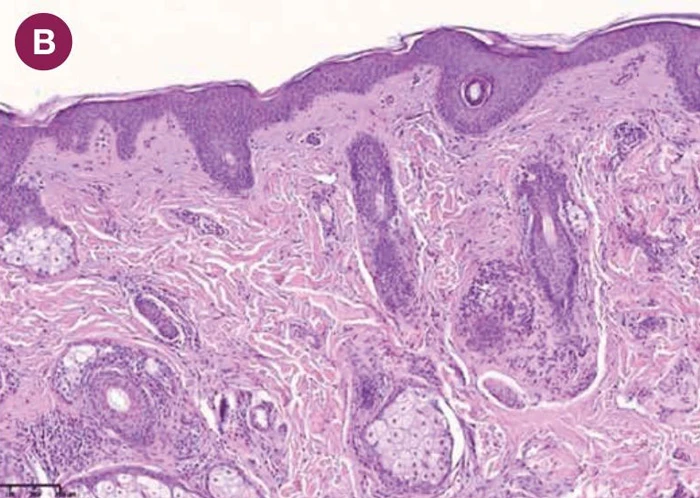

После применения нативной ГК (Hyon 1,8 %) наблюдались выраженные структурные изменения. В микросрезах отмечено утолщение эпидермиса, преимущественно за счет шиповатого слоя, увеличение толщины сосочкового слоя дермы (рис. 3 А, B). В сосочковом слое было отмечено повышение плотности клеточных элементов. В сетчатом слое визуализировались крупные пучки коллагеновых волокон (рис. 3 C, D).

увеличение толщины сосочкового слоя дермы

крупные пучки коллагеновых волокон

После применения нативной ГК морфологические изменения сосочкового и сетчатого слоя дермы могут быть обусловлены созданием благоприятной для синтеза среды для фибробластов (с повышением сигналинга), а изменения эпидермиса — улучшением кровоснабжения дермы и доставки питательных веществ к эпидермису через дермо-эпидермальную границу.